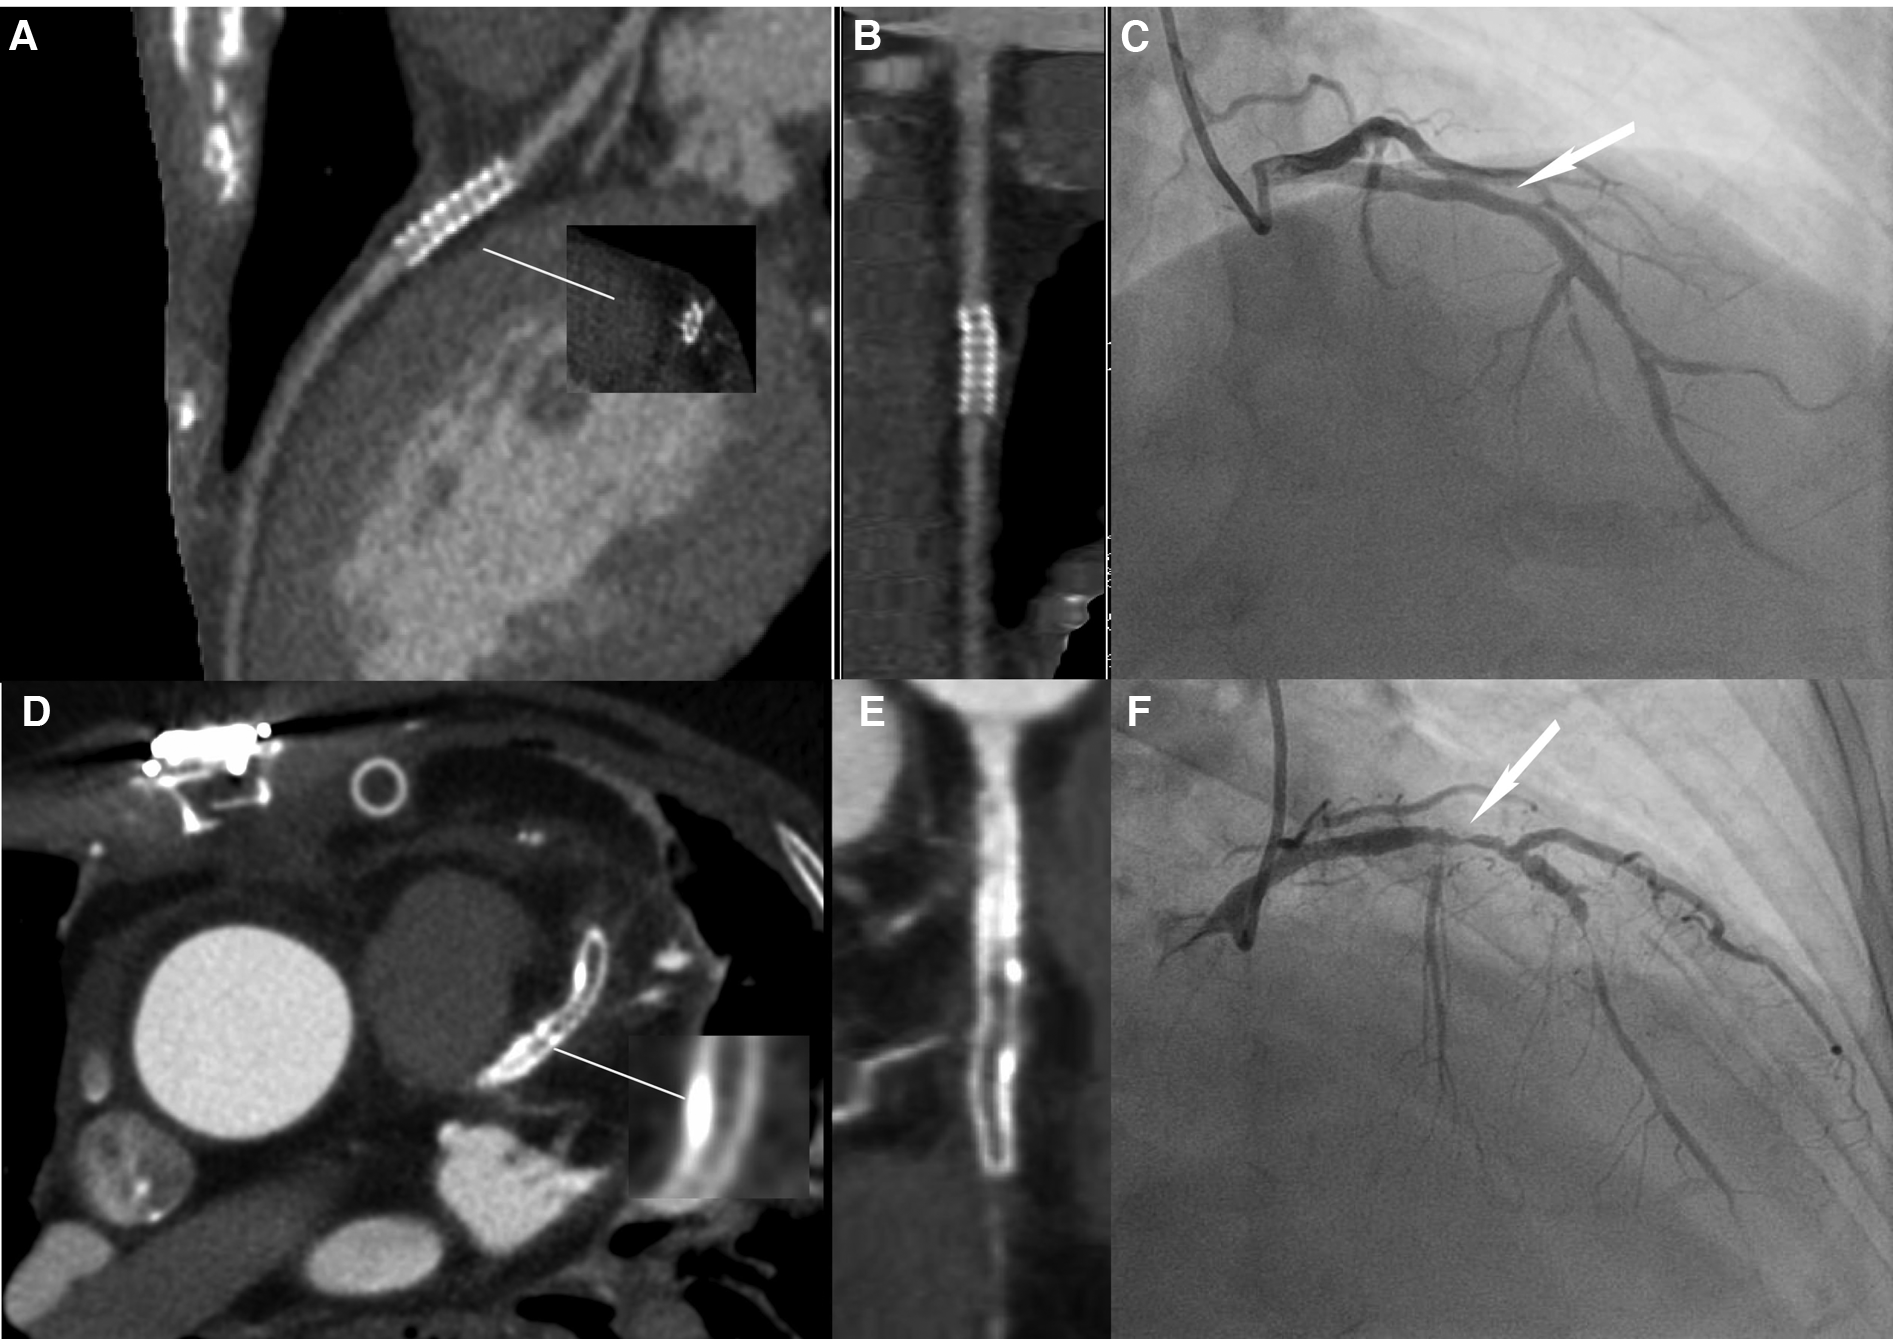

Figure 3

Image quality comparison between the LD and HD groups. (A–C) A 63-year-old male patient in the HD group, with a BMI of 24.53 kg/m2. (A) The image quality of CCTA reached a subjective score of 3: with minimal stent margin definition, some blooming artifacts, acceptable diagnostic information, and an image noise of 37.7 HU. (B) CPR image of LCX showed the absence of ISR in a 2.5 mm coronary stent (resolute, 2.5 × 21 mm, JHLD). (C) ICA of LCX confirmed the absence of ISR (white arrow). (D–F) A 61-year-old male patient in the LD group with a BMI of 24.06 kg/m2. (D) The image quality of CCTA reached a subjective score of 5: clear stent strut definition with a clear border of the blood vessel and an image noise of 16.7 HU. (E) CPR image of LAD showed focal ISR in a 3.0 mm coronary stent (resolute, 4.0 × 33 mm, RDES). (F) ICA of left anterior descending the diagnosis of focal ISR (white arrow). CCTA, coronary computed tomography angiography; CPR, curved planar reformation; ICA, invasive coronary angiography; ISR, in-stent restenosis; LCX, left circumflex; LAD, left anterior descending.